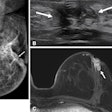

False-negative breast exams on the rise